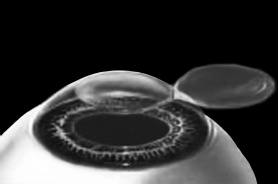

ЛАСИК – основной метод лазерной коррекции в мире в настоящее время. По большому счету, ФРК и ЛАСИК – единственные методы коррекции. Остальные методы являются либо модификациями ФРК и ЛАСИК, либо «компромиссом» между ними. Эпителий роговицы не трогают, так как он – залог быстрого заживления. Накладывают на глаз вакуумное кольцо – стальную присоску кольцевидной формы с присоединенной к нему трубочкой. Через трубочку из присоски отсасывается воздух, чтобы создать относительный вакуум. Отсасывает воздух главный аппарат для проведения ЛАСИКа – микрокератом. Это прибор размером с коробку из-под обуви. Его предназначение – срезание поверхностной крышки роговицы. К глазу присоединяют вакуумное кольцо, окружающее роговицу. Глаз четко фиксируется относительно кольца и сдвинуться с места может только с кольцом, в отверстие которого выступает купол роговицы. Затем к кольцу присоединяется головка микрокератома. Это второй инструмент микрокератома и соединяется с ним или шнуром, или тонким шлангом. Головка крепится на турбине, и вместе они имеют вид толстой шариковой ручки с обрубленным концом. Эту «ручку» хирург держит в правой руке, а вакуумное кольцо – в левой. Эта «ручка» нужна, чтобы сформировать крышечку роговицы. Внутри головки есть очень острое одноразовое лезвие. Турбина, соединенная с головкой, может двигать одноразовое лезвие туда-сюда, пилящими движениями. Можно резать роговицу, как хлеб, – пилящими движениями. И тут самое главное – скорость. Одноразовое лезвие делает 15000 пилящих движений в минуту. При такой скорости назвать это срезанием роговицы уже трудно, скорее это отслаивание верхних слоев. ![]() Рис. 3. Схема формирования роговичного лоскута с помощью микрокератома. Иллюстрация с сайта Международного лазерного центра www.optics.ru Итак, головка присоединяется к вакуумному кольцу и по специальным полозьям двигается над куполом роговицы (рис. 3). Срез, или отслаивание (называйте, как хотите), проводится не полностью, у крышечки (роговичного лоскута) остается маленький участок на периферии, соединяющий ее с роговицей (рис. 4). ![]() Рис. 4. Роговичный лоскут сформирован. Иллюстрация с сайта Международного лазерного центра www.optics.ru После формирования роговичного лоскута убирают инструменты микрокератома, затем шпателем откидывают его вбок (рис. 5). Обнажается роговичное ложе, то есть место, на котором лежал лоскут. Это верхние слои стромы роговицы. Ложе осушают тупфером и так же, как и при ФРК, настраивают лазер и испаряют несколько микрон вещества стромы (рис. 6). Потом промывают строму водой и шпателем укладывают лоскут на место. ![]() Рис. 5. Роговичный лоскут откинут в сторону. Иллюстрация с сайта Международного лазерного центра www.optics.ru ![]() Рис. 6. Луч эксимерного лазера испаряет на роговичном ложе несколько микрон стромы роговицы. Иллюстрация с сайта Международного лазерного центра www.optics.ru Стоит один раз моргнуть и лоскут скомкается и зрения не будет. Его бы пришить на место. Но швы деформируют роговицу. Все проще. Лоскут разглаживают мокрым тупфером, прижимая его ровненько к старому месту (рис. 7 и 8). Только место не старое, с роговичного ложа удалили несколько микрон в виде причудливой ямки (при коррекции близорукости). ![]() Рис. 7. При коррекции близорукости на роговичном ложе формируется «ямка». Иллюстрация с сайта Международного лазерного центра www.optics.ru ![]() Рис. 8. Роговичный лоскут укладывается на место. Иллюстрация с сайта Международного лазерного центра www.optics.ru Края роговичного лоскута осушают сухим тупфером. Влага, оставшаяся под лоскутом в ямке роговичного ложа, высасывается в тупфер. Лоскут притягивает к ложу, как вакуумную присоску. Вакуумом начали, вакуумом закончили. Ждем, когда закончится приживление лоскута к ложу. Эпителий цел и невредим. А значит, никаких болей. Около трех часов возможны слезотечение и светобоязнь. И все (рис. 9). ![]() Рис. 9. Форма роговицы до проведения коррекции (а) и после коррекции близорукости (б). Испарение нескольких микрон толщины роговицы привело к уменьшению ее кривизны в центре. Иллюстрация с сайта Международного лазерного центра www.optics.ru Хирурги о ЛАСИКе говорят: «90 % хирургии и 10 % долечивания». Лазерный субэпителиальный кератомилез (LASEK) Модификация ФРК. Чтобы укоротить неприятный послеоперационный период, эпителий, обработанный спиртовым или солевым раствором, отслаивают очень бережно, с помощью специальных инструментов, в виде цельного лоскута. А после испарения эксимерным лазером боуменовой мембраны и нужного количества слоев стромы этот эпителиальный лоскут укладывают обратно и, чтобы он не сместился, прижимают мягкой контактной линзой. Через 3–4 дня эпителий заживает, а благодаря линзе и даже еще не приживленному эпителиальному лоскуту боль и светобоязнь не беспокоят пациента с первых часов после коррекции, а зрение восстанавливается на пару недель быстрее, чем при ФРК. Также одной из модификаций ФРК является MAGEK. Основным отличием от ФРК является применение препарата Митомицин С (Mitomycin-С), который блокирует «слишком быстрое деление клеток» и снижает риск возникновения хейза. Эпи-ЛАСИК (Epi-LASIK) Нечто среднее между ЛАСИК и LASEK. Для отделения эпителия используются не спиртовой или солевой растворы, а специальный аппарат, очень похожий на микрокератом. Аппарат называется эпикератомом. Он отслаивает эпителий вместе с частью боуменовой мембраны в виде лоскута, похожего на лоскут при ЛАСИКе, только гораздо тоньше. После проведения коррекции лоскут также прижимают контактной линзой. Но не поврежденный химическим ожогом эпителиальный лоскут, да еще с остатками боуменовой мембраны, значительно сокращает период заживления и восстановления и снижает другие недостатки ФРК и LASEK, о которых будет сказано ниже. Рефракционный эксимерлазерный интростромальный кератомилез (РЭИК) |